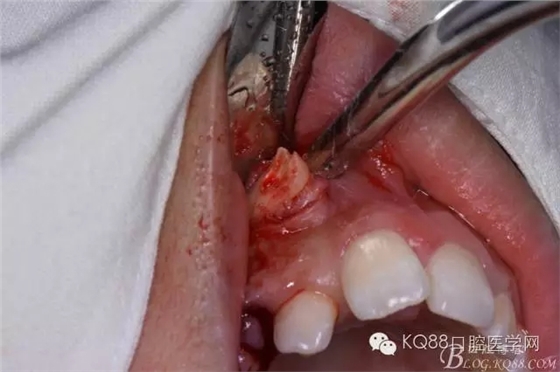

患者、女、高xx、17歲,主訴:外院轉診要求拔除埋伏牙。??茩z查:53殘根滯留、牙根斷面位于齦下,cbct檢查:13高位埋伏,牙冠壓迫12牙根的遠中面,牙根未見吸收,經(jīng)我院正畸科會診,建議拔除13、53,然后再正畸治療。患者同意治療方案,術前簽知情同意書。 拔牙過程: 圖1.術前的cbct檢查:13位于12遠中根尖區(qū),13牙根接近上頜竇、53牙根滯留。 圖2.口內(nèi)觀:53滯留、牙根斷面位于齦下,12牙冠唇傾。 圖3.合面觀:12畸形舌側窩、腭側沒有明顯隆起 圖4.首先拔除53,然后在23唇側區(qū)域的前庭溝處的黏膜做弧形切口 圖5. 翻瓣 圖6.去骨 圖7.暴露出13牙冠 圖8.高速渦輪機分牙、目的是盡量少去骨。 圖9. 從頸部截分13 圖10. 13牙冠頸部分牙情況 圖11.再把牙冠分成近中、遠中兩部分。 圖12.取出13牙冠 圖14.取出13牙根 圖15.取出的13的牙根 圖16.拔除13牙后形成的拔牙創(chuàng)。 圖17.拔除的13. 圖18.縫合